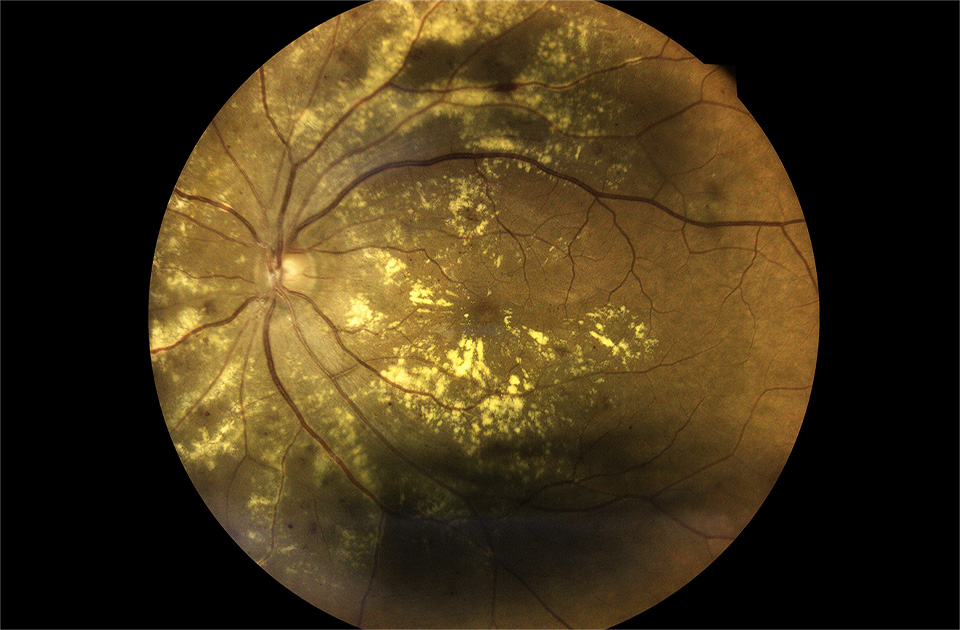

糖尿病性網膜症

糖尿病網膜症は、糖尿病の慢性合併症の一つであり、網膜微小血管症と神経障害を特徴とする疾患です。高血糖状態が持続することで、網膜血管の透過性亢進、微小動脈瘤形成、出血、硬性白斑形成などが生じ、最終的には新生血管形成を伴い、黄斑浮腫や硝子体出血により視力障害をきたします。

糖尿病性網膜症の原因

糖尿病になると、血液の中の糖が血管を傷つけてしまうことがあります。特に目の奥にあるとても細い血管は、この糖の影響を受けやすく、傷ついてしまいます。傷ついた血管は、栄養をうまく運べなくなり、新しい血管ができてしまいます。この新しい血管はとてももろく、出血しやすいため、出血することにより視界がぼやけるなどの症状が出てくることがあります。

糖尿病性網膜症の症状

初期には自覚症状がないことが多いのですが、目の中を詳しく調べると、少しずつ変化が見られます。病気 が進むと、視界がぼやける、物が二重に見えるなど、視力に変化が現れることがあります。さらに悪化すると、視界に黒い影が見えたり、光がちらついて見えたりすることもあります。放置すると、失明してしまうこともあるので、早期発見・早期治療、定期的な経過観察が大切です。